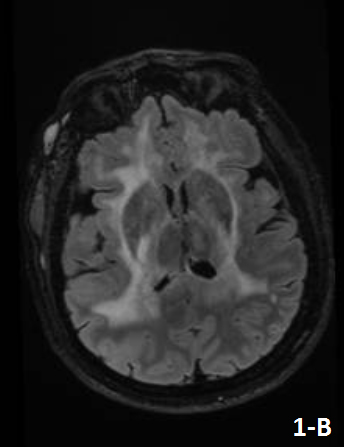

Figure 1 and Figure 2 showed the results of a brain MRI performed at admission, revealing an extensive lesion that involved the periventricular, subcortical and deep white matter.

Neuroradiological features often show an extensive compromise of the white matter with a slight mass effect at both supratentorial and infratentorial levels, in some cases spreading along the corticospinal tract and/or compromising gray matter.

Figure 1. Fluid Attenuated Inversion Recovery (FLAIR) sequence showed an extensive lesion affecting primarily the subcortical and deep white matter at frontal (a), parieto-insular and callosal (b) and temporal levels (c).

A diffuse hyperintensity was also observed at infratentorial levels, affecting primarily the midbrain (d). At the level of the right temporal epicranial soft tissue region, a lesion with heterogeneous signal and multiple dilated vascular structures were found, in relation to the patient’s prior history of congenital facial hemangioma.